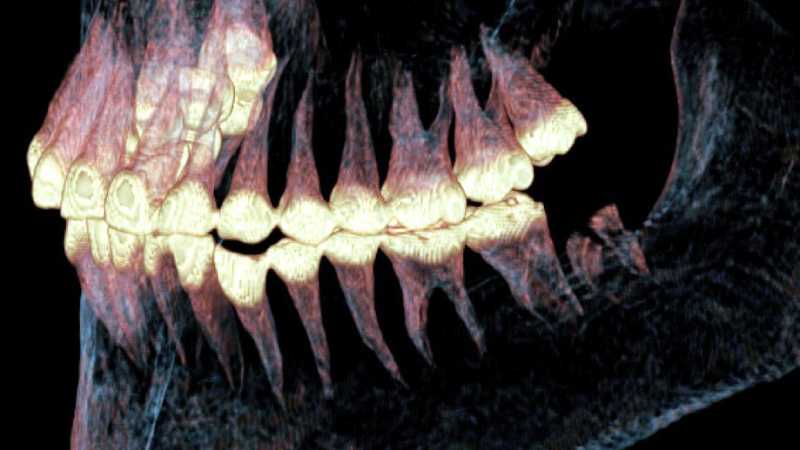

“The CT scan worked like a true time machine. It allowed us to examine the skull without damaging it and create an extremely accurate three-dimensional digital model,” the scientist explained.

Based on 551 tomographic slices, the researchers digitally reconstructed the skull and identified clear signs of trauma and surgical intervention.

The images revealed that the woman suffered a violent impact on the right side of the skull, which depressed the temporal bone by between 6 and 8 millimeters. The blow destroyed the right temporomandibular joint — responsible for the movements of the jaw.

The researchers found two small channels drilled into the bone, each about 1.5 millimeters in diameter. One of them passed through the head of the mandible and the other through the zygomatic process of the temporal bone.

These channels met at a right angle, forming a planned structure.

One of the most impressive pieces of evidence from the study is that the bones around the holes healed. The CT scan showed a ring of bone tissue formed around the drilled channels, a clear sign that the surgery took place while the woman was still alive.